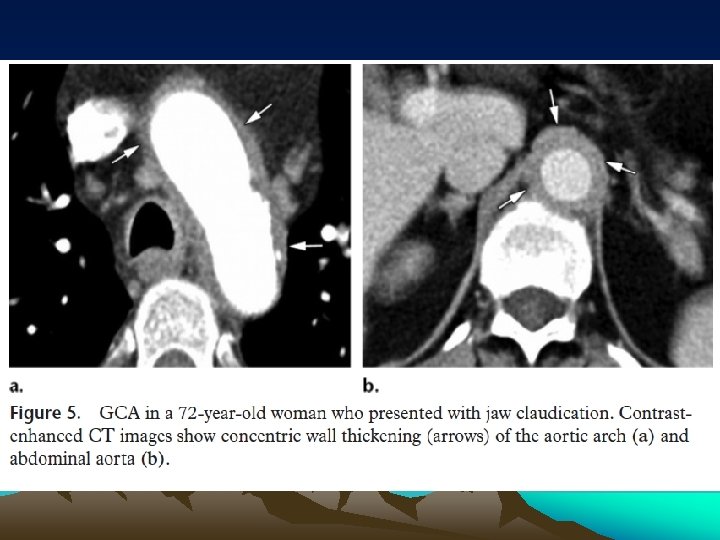

• At histologic analysis, GCA appears similar to Takayasu arteritis • The principal CT and MR imaging appearance of GCA is similar to that of Takayasu arteritis, with evidence of arterial wall thickening (Fig 5), stenosis, and aneurysm • Aortic GCA typically remains asymptomatic during the early phase of the disease and causes serious late complications like aneurysms and dissections